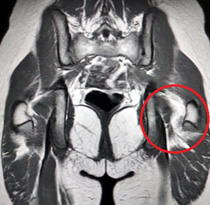

Christyna Seiko is misdiagnosed with growing pains in her knees and thighs for over four months before a chiropractor finds that she has a dislocated hip that created an inch difference in the length of her left leg. She has instant relief when it was popped back in place, but she suffers cascading injuries from her hips to her ankles throughout the year. She last runs in February, joining her older sister in limited cycling for conditioning the rest of the year.

Abuse from outside tennis coaches/officials result in serious injury in August that limit her time on court for months, while attempts to compensate for the pain in her legs continue the vicious cycle of again straining her hip. Her physical trials culminate in a complete, grade 3 ruptured hip flexor that ends her tennis campaign in November and puts Christyna Seiko out for three months!